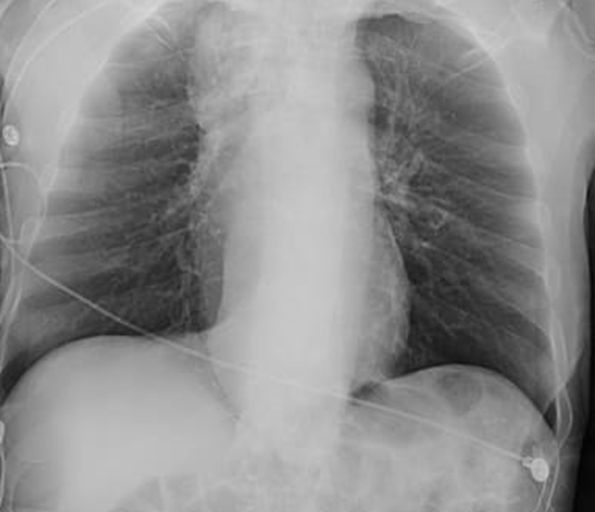

Figure 1. Chest Radiograph

Caption: Frontal chest radiograph demonstrates a widened right upper mediastinum with double density along the right heart border, suggestive of a dilated esophagus.

On chest X-ray, the most prominent abnormality was identified in the mediastinum.

1. Correct Answer: (2) Mediastinum

Explanation: The X-ray reveals widening of the upper right mediastinum with double contour, indicative of esophageal dilation, which is best visualized in the mediastinal silhouette.